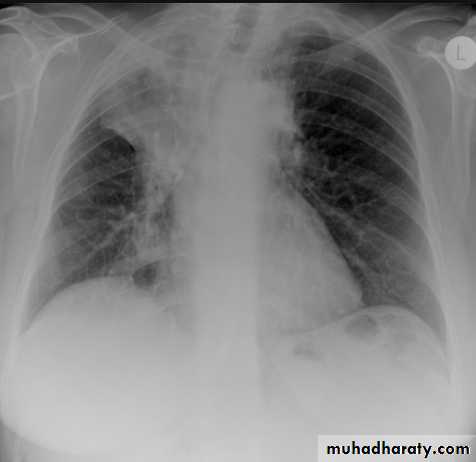

Left lower lobe collapse has distinctive features, and can be readily identified on frontal chest radiographs, provided attention is paid to the normal cardiomediastinal contours. The shadow cast by the heart does however make it harder to see than the right lower lobe collapse

Radiographic features

Left lower lobe collapseis readily identified in a well penetrated film of a patient with normal sized heart, but can be challenging in the typical patient with collapse, namely unwell patients, with portable (AP) often under-penetrated films, often with concomitant cardiomegaly. Features to be observed include :

triangular opacity in the posteromedial aspect of the left lung

edge of collapsed lung may create a 'double cardiac contour'

left hilum will be depressed

loss of the normal left hemidaphgragmatic outline

loss of the outline of the descending aorta

Non-specific signs indicating left sided atelectasis are usually also be present including:

elevation of the hemidiaphragm

crowding of the left sided ribs

shift of the mediastinum to the left

On lateral projection the left hemidiaphragmatic outline is lost posteriorly and the lower thoracic vertebrae appear denser than normal (they are usually more radiolucent than the upper vertebrae) .